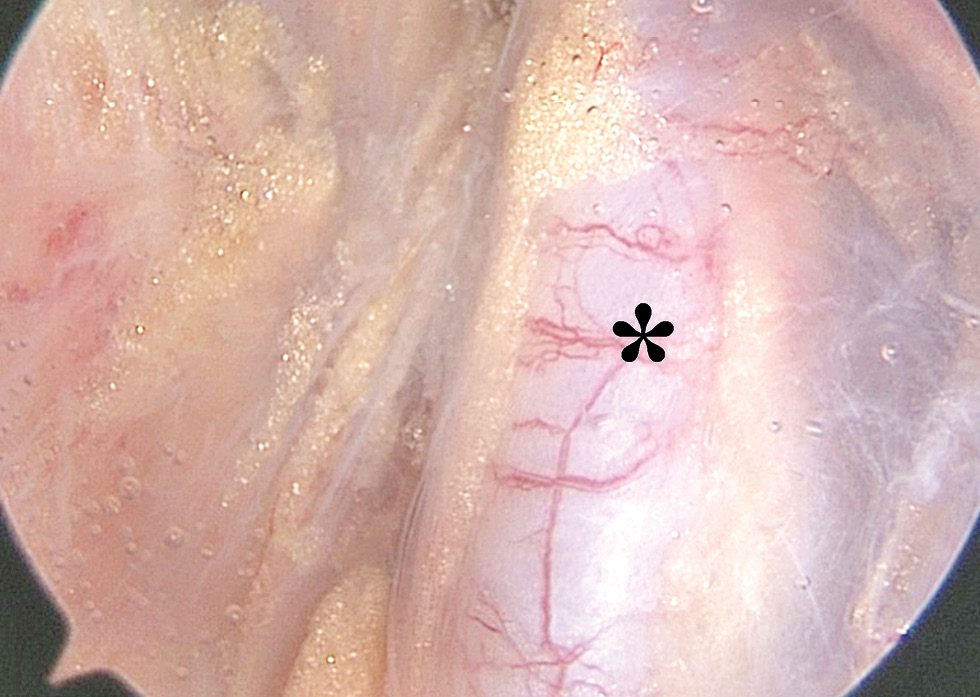

Рис. 9. Плечевое сплетение (*) в области межлестничного пространства.

Fig. 9. Brachial plexus (*) at interscalene space.

Декомпрессия сплетения заключалась в рассечении всех спаечных и рубцовых тканей кпереди, кверху и кзади от стволов ПС. Это позволило сформировать свободное пространство вокруг ПС для устранения его компрессии и ирритации. Интраоперационные фото ПС после выполнения декомпрессии представлены на рис. 12, 13.

Рис. 12. Плечевое сплетение (*) в области межлестничного пространства после выполнения декомпрессии.

Fig. 12. Brachial plexus (*) at interscalene space after decompression.